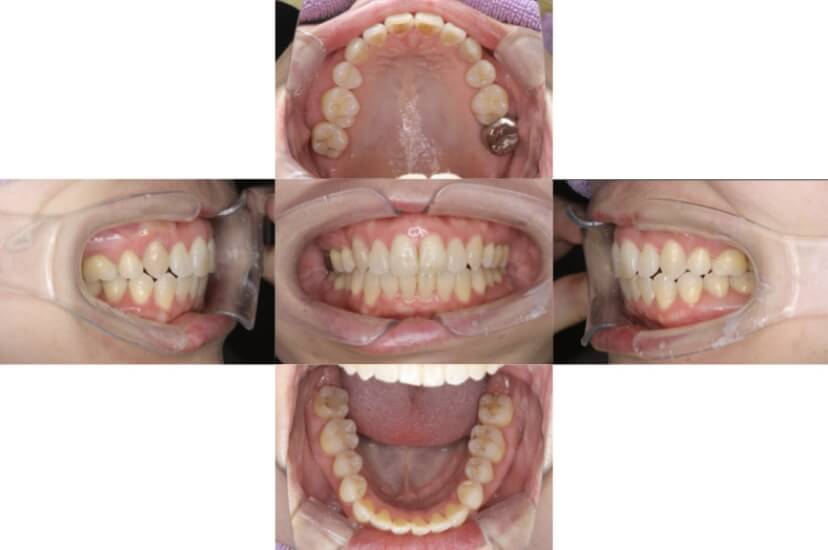

AFTER

上下顎叢生(上下の前歯のガタガタ)のケースです。

装置はラビアル(上下表側)で、上下顎の小臼歯を4本抜歯を行っています。抜歯したスペースを使って、上下の前歯の後方移動と叢生(ガタガタ)の改善を行っています。

主訴 歯並びが悪く、舌を噛んでしまうのを治したい。

年齢・性別 27歳 男性

お住まいの地域 東京都大田区

治療方針 抜歯スペースを利用して上下前歯の叢生(ガタガタ)の改善

抜歯部位 上下顎左右第一小臼歯

使用装置 ラビアル(上下表側)、顎間ゴム

治療期間 3年1か月

治療回数 30回